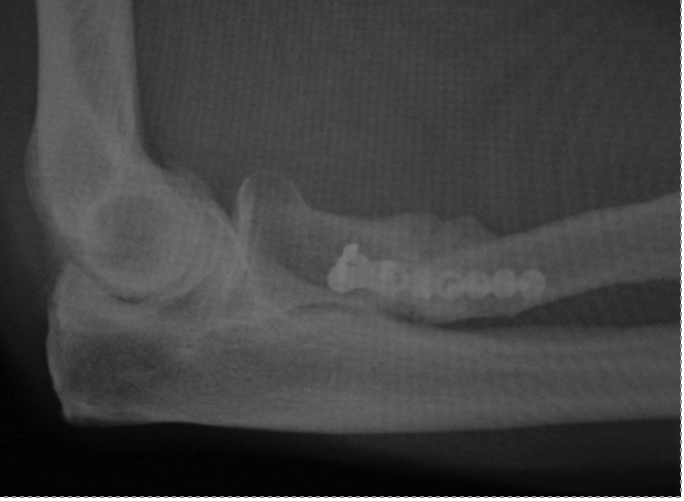

However, there are no reports in the literature on proximal radial fracture through the repair site. This is the first report of a proximal radial fracture after the patient under-went repair and subsequent revision repair of a distal biceps tendon rupture via a 2-incision approach.